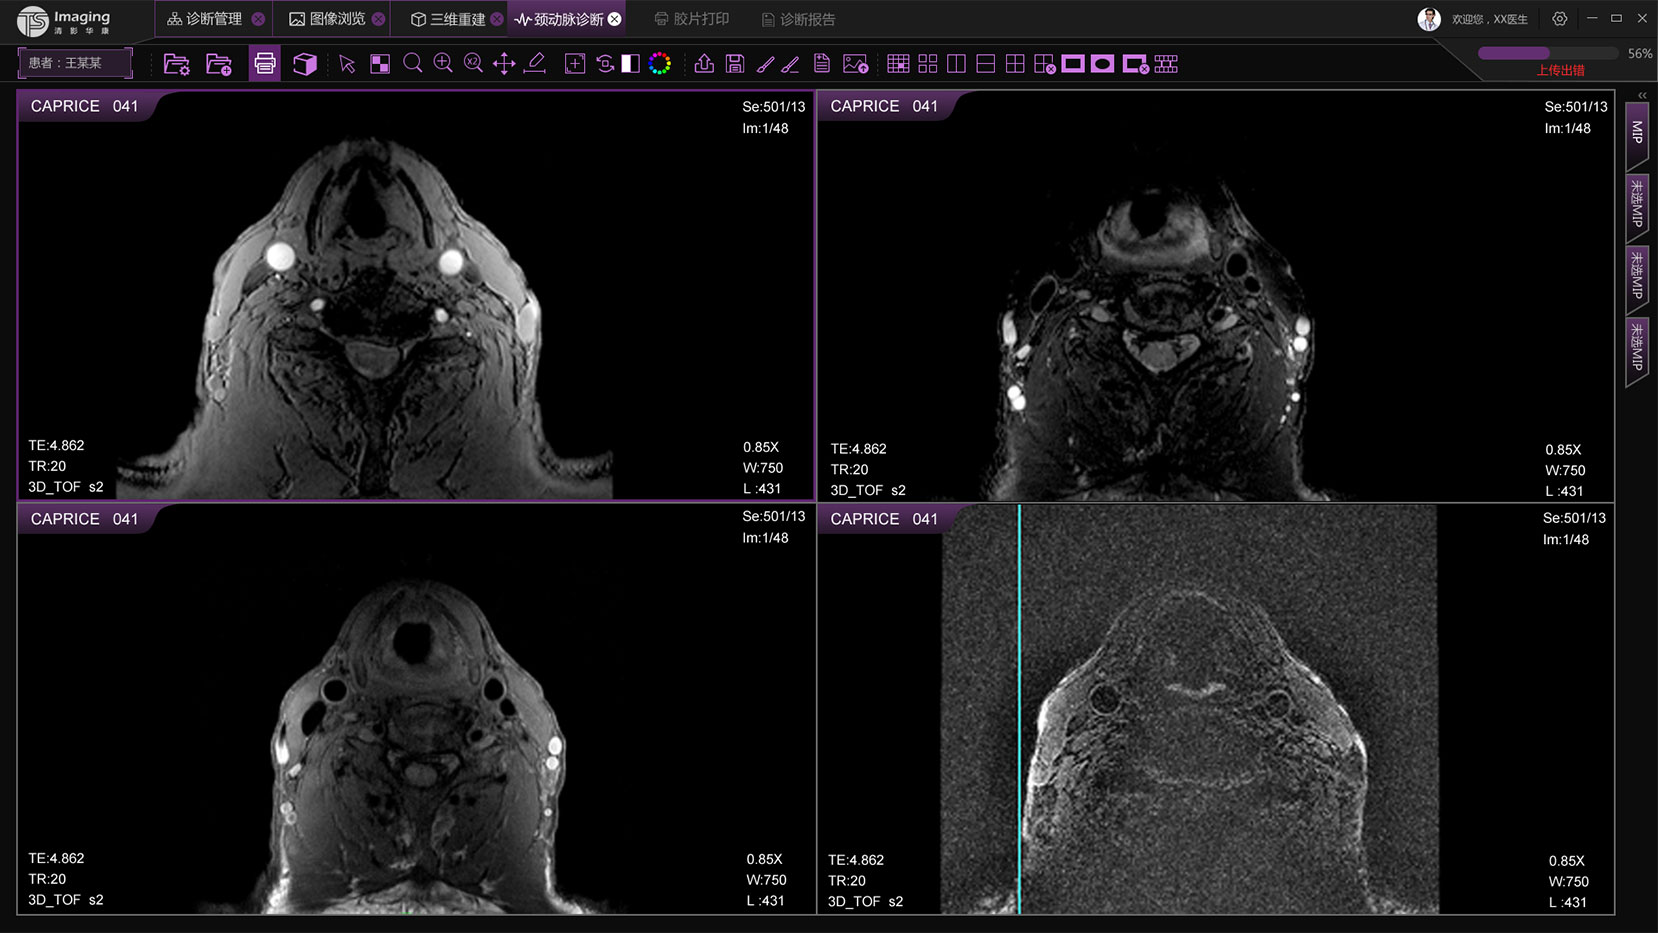

頸動(dòng)脈診斷頁面

頸動(dòng)脈診斷頁面整體布局和三維重建比較相似,最大的區(qū)別是右側(cè)的操作區(qū)域,血管分析都為按鍵操作,通過間隔的大小分成三部分。單層切片除了按鍵還有下拉菜單的操作。

頸動(dòng)脈診斷原型